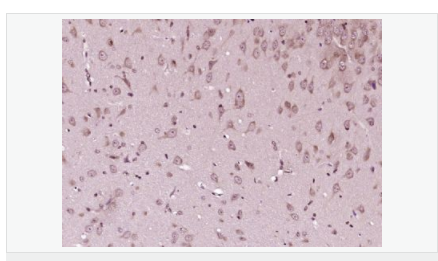

P27蛋白是一種新發(fā)現(xiàn)的周期素依賴激酶抑制劑,屬于細胞周期的負性調控因子。P27基因及其產物的異常表達可能與某些腫瘤的發(fā)生、發(fā)展有著密切的關系。P27蛋白對細胞周期的調控及在腫瘤中發(fā)揮著很重要的作用。

image.png